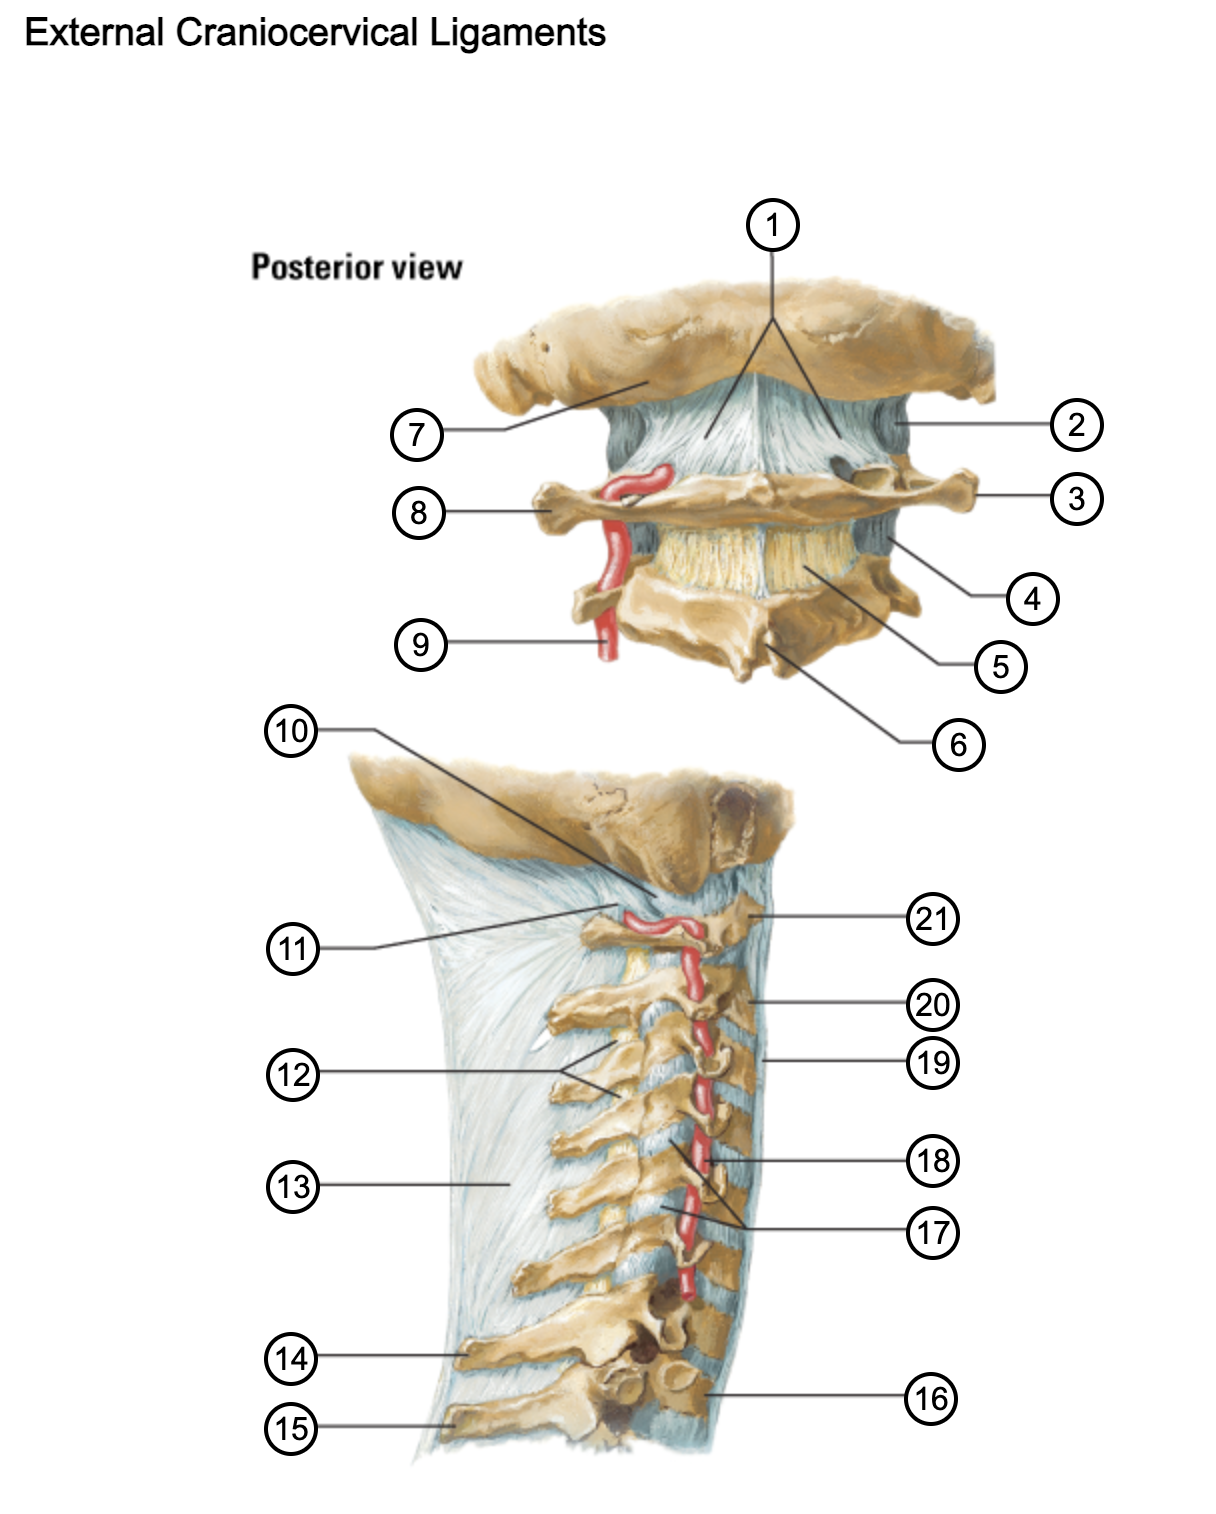

1

posterior antlantooccipital membrane

2

capsule of atlantooccipital joint

3

transverse process of atlas (C1)

4

capsule of lateral atlantoaxial joint

5

ligamenta flava

6

spinous process

7

occipital bone

8

transverse process of atlas (C1)

9

vertebral artery

10

capsule of atlantooccipital membrane

11

posterior atlantooccipital membrane

12

ligamenta flava

13

nuchal ligament

14

spinous process of C7 vertebra

15

spinous process of T1 vertebra

16

T1 vertebra

17

zygapophysical joints (C4-5 and C5-6)

18

vertebral artery

19

anterior longitudinal ligament

20

body of axis

21

Atlas (C1)